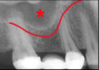

what happens if the Frankfort plane is positioned to high or low on a panoramic radiograph?

A

• too high: the chin is positioned too high and there is a reverse smile line with the maxillary incisors blurred

• too low: the chin is positioned too low and there is an exaggerated smile with mandibular incisors blurred - condyles may not be visible